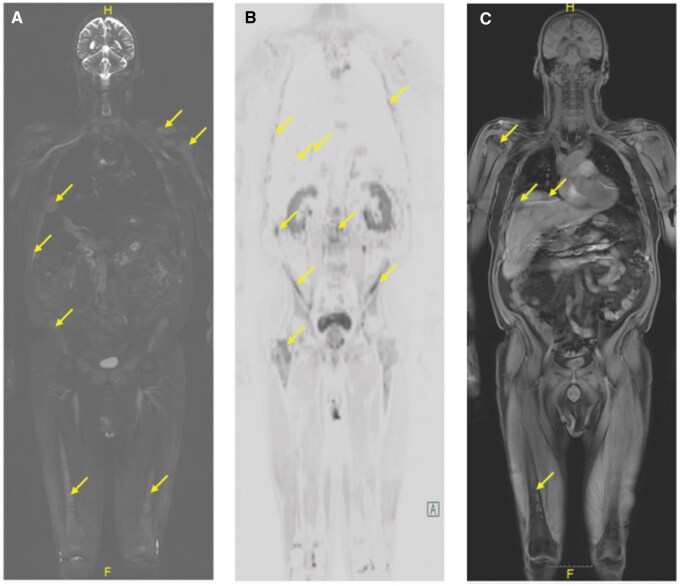

多发性骨髓瘤是一种浆细胞疾病,除了骨髓瘤疾病的其他体征外,还可导致标志性的骨破坏性变化。影像通常有助于确定诊断和患者分期。有几种不同的成像方式可以提供对疾病程度的不同程度的了解。我们报告了一个独特的多发性骨髓瘤病例,其中患者疾病的进行性突出了不同成像方法的优势和局限性。全身MRI是一种非对比成像技术,可以直接对骨髓空间进行成像,从而可以在皮质和小梁破坏性变化发生之前进行疾病检测。通过这样做,全身MRI提供了远远超过传统平片甚至CT的洞察力。利用多种不同成像方式(平片、CT、PET-CT和全身磁共振成像)的发现,我们将讨论成像如何帮助临床医生更好地评估患者的疾病负担,并补充传统疾病监测的基础(血清学、活检组织病理学、直接临床检查和观察)。

Multiple Myeloma represents a plasma cell disorder that can result in hallmark bony destructive change in addition to other signs of myelomatous disease. Imaging often helps in establishing the diagnosis and staging the patient. There are several different imaging modalities that can provide different levels of insight into the disease extent. We report a unique case of multiple myeloma where the progressive nature of the patient's disease highlights the strengths and limitations of the different imaging approaches. Whole-body MRI represents a noncontrast imaging technique that directly images the bone marrow space, allowing for disease detection that can precede the onset of cortical and trabecular destructive changes. In so doing, whole-body MRI provides a level of insight that far exceeds traditional plain films and even CT. Using the findings from many different imaging modalities (plain films, CT, PET-CT, and whole-body magnetic resonance imaging), we will discuss how imaging can help clinicians to better assess the patient's disease burden and complement the foundations of traditional disease monitoring (serology, histopathology from biopsy, direct clinical exam, and observation).